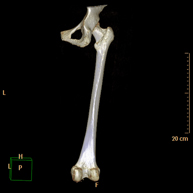

Exploració radiològica que mitjançant un sistema de raigs X i detectors que giren al voltant del pacient i que reconstrueixen les imatges per ordinador (TC Multidetector), permet l'estudi detallat dels ossos llargs (tíbia, peroné, fèmur, húmer, radi i cúbit). - Biòpsia òssia guiada per TC

Prova diagnòstica no invasiva que consisteix en l'estudi vascular del sector aorto-ilíac i dels vasos arterials d'ambdues extremitats inferiors i l'obtenció d'imatges d'alta definició anatòmica mitjançant l'ús d'un equip de TC Multidetector d'última generació i de contrast iodat. La qualitat de les imatges permet realitzar reconstruccions en 2D i 3D gràcies a estacions de treball especialitzades en l'estudi arterial.